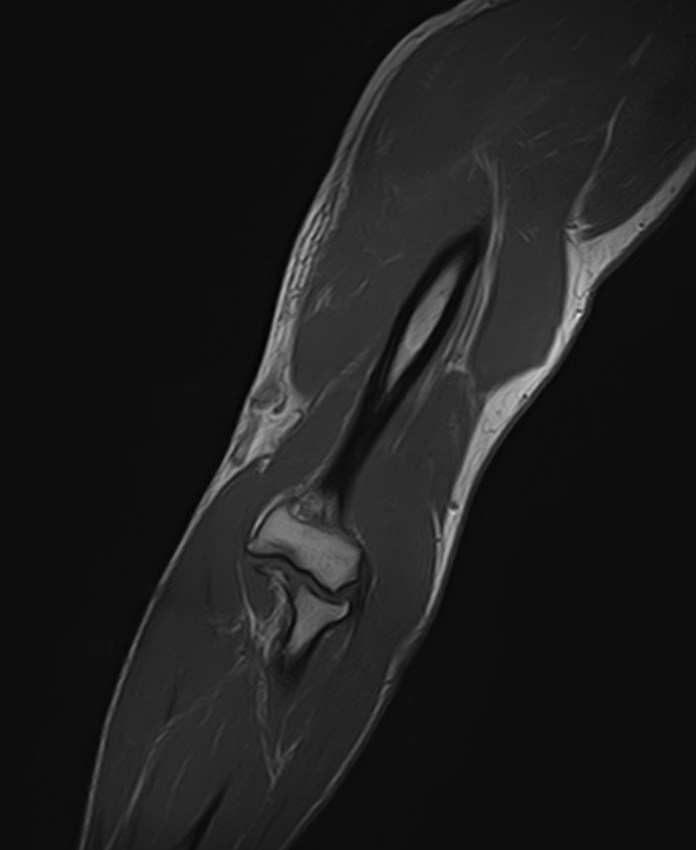

Магнитно-резонансная томография применяется для обследования мягких тканей верхних и нижних конечностей, включая кожу, подкожно-жировую клетчатку, мышцы, фасции, межфасциальные пространства, сухожилия, связки, сосудистую систему, лимфоузлы и лимфатические протоки, нервные волокна, надкостницу и костный мозг.

Кроме того, имеет значение показатель индукции магнитного поля томографа. Наша клиника оснащена современным высокопольным томографом последнего поколения TOSHIBA VANTAGE TITAN 1,5 Тесла. Высокая индукция магнитного поля обеспечивает повышенную четкость изображений при обследовании мягких тканей конечностей. За счет послойного сканирования в различных плоскостях с шагом от 1 мм и последующего преобразования данных в объемные изображения томограф обеспечивает выявление мельчайших изменений в тканях. Это позволяет проводить диагностику различных заболеваний на самых ранних стадиях.